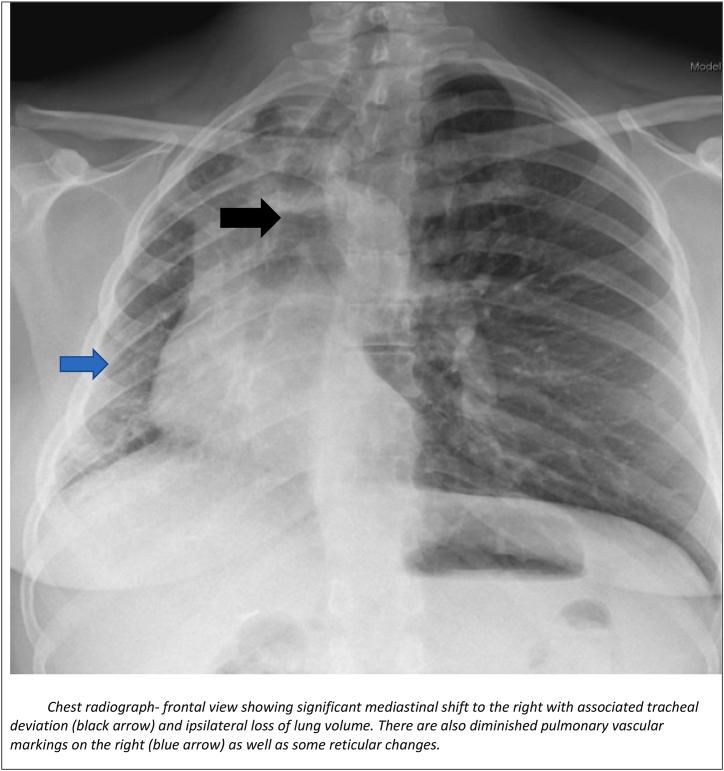

Unilateral absence of pulmonary artery (UAPA) is a congenital clinical abnormality that is rarely diagnosed in adulthood. Due to its rarity and heterogeneity as it pertains to its clinical presentation, it may be difficult to diagnose, often leading to misdiagnosis. We present a case of UAPA with unilateral pulmonary fibrosis which was misdiagnosed as rheumatoid arthritis-associated interstitial lung disease (RA-ILD). We describe the symptomology, physical examination findings, laboratory values and radiologic findings. We also describe the diagnostic challenges and approach to a patient presenting with unilateral interstitial lung disease (ILD) and highlight the importance of a comprehensive evaluation.

单侧肺动脉缺如(UAPA)是一种先天性临床异常,在成年期很少被诊断出来。由于其罕见性以及临床表现的异质性,可能难以诊断,常常导致误诊。我们报告一例伴有单侧肺纤维化的UAPA病例,该病例最初被误诊为类风湿关节炎相关间质性肺病(RA-ILD)。我们描述了症状、体格检查结果、实验室检查值和影像学检查结果。我们还描述了诊断面临的挑战以及对单侧间质性肺病(ILD)患者的诊断方法,并强调了综合评估的重要性。